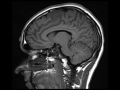

Low-grade Astrocytoma

28-year-old male with new onset seizure activity on the right. There is an infiltrating nonenhancing mass centered within the left superior frontal gyral subcortical white matter with infiltration of the overlong cortical grey matter. The lesion is T2/FLAIR hyperintense, T1 hypointense, and does not restrict on the diffusion weighed images. There is swelling of the left superior frontal gyrus with effacement of the surrounding cortical sulci. This is a case of a biopsy proven infiltrating grade 2 astrocytoma. Seizure is the most common presenting feature of low-grade gliomas. 2/3rds of cases involve the supratentorial white matter, with the frontal lobes affected in 1/3 of cases.